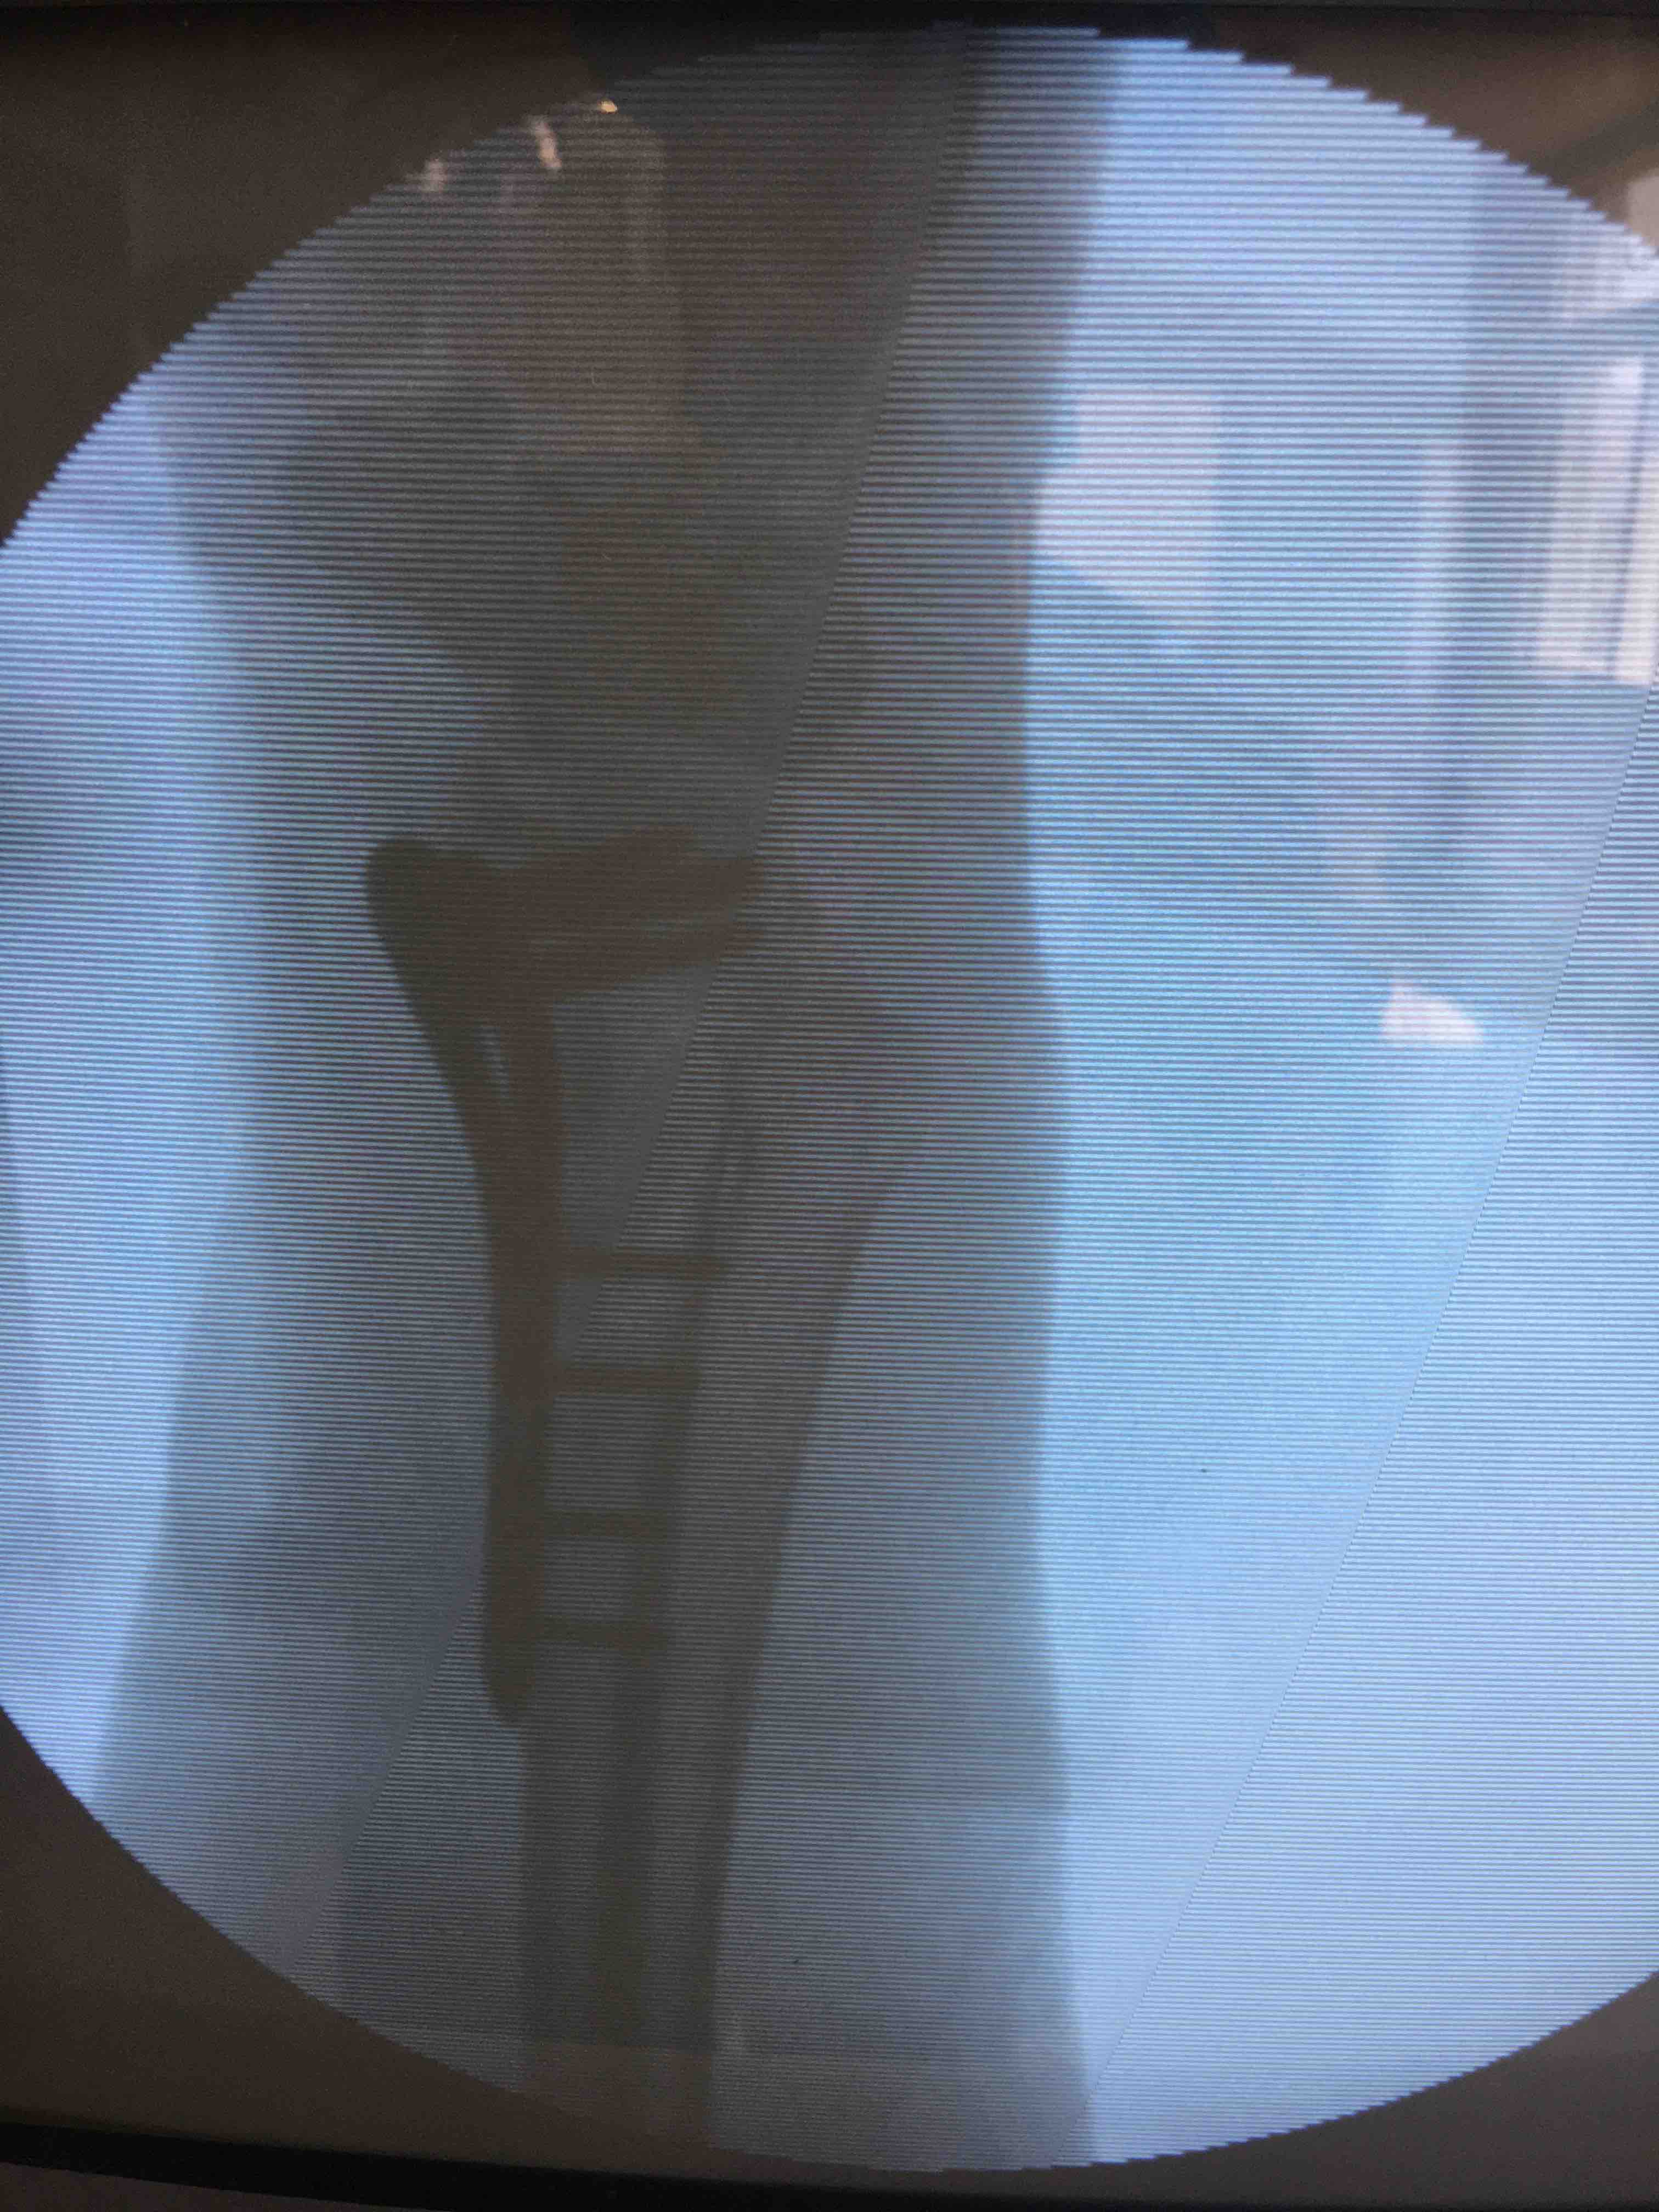

切开复位内固定术,术后抗炎,消肿等处理。